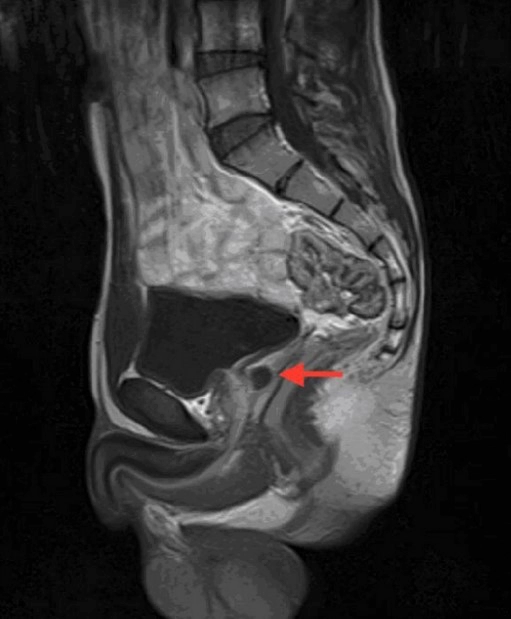

낭종이 클 경우, 미세 침습 수술이 선택될 수 있습니다. 이러한 수술은 초음파, 컴퓨터 토모그래피 (CT) 스캔, 자기 공명 영상 (MRI) 등의 가이드 하에 수행됩니다. 이 과정에서 의사는 작은 침을 통해 낭종으로 가는 길을 만들고, 그 후에 이 침을 통해 낭종에 들어가 액체를 배출합니다. 이렇게 하면 낭종의 크기가 줄어들고 증상이 완화됩니다.